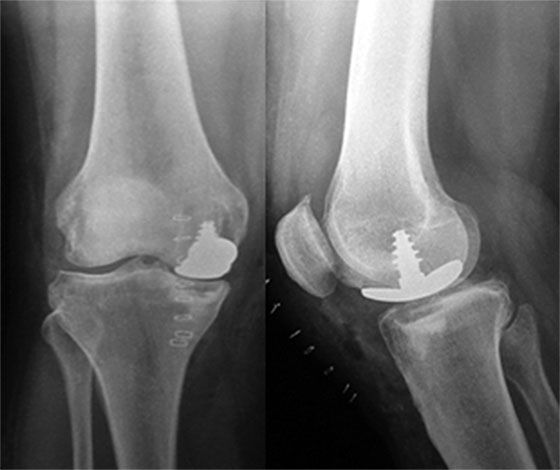

El control radiológico demuestra la congruencia del implante con la superficie ósea, la cual restaura la anatomía del cóndilo femoral (Fig. 6).